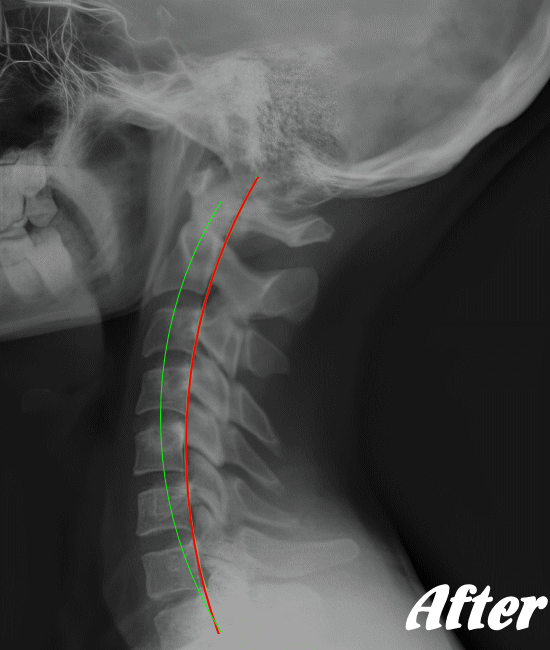

身体に無理をかけず骨や関節の位置を解剖学的に正しい位置へ調整することで、痛みを取り除いていきます。慢性化した痛みも改善します。

多くの場合、頸椎(首の骨)、肩甲骨、背中の胸椎(背骨)、肋骨、そして骨盤(仙腸関節)を調整すれば、痛みは早い段階でなくなり、健康な状態に回復します。